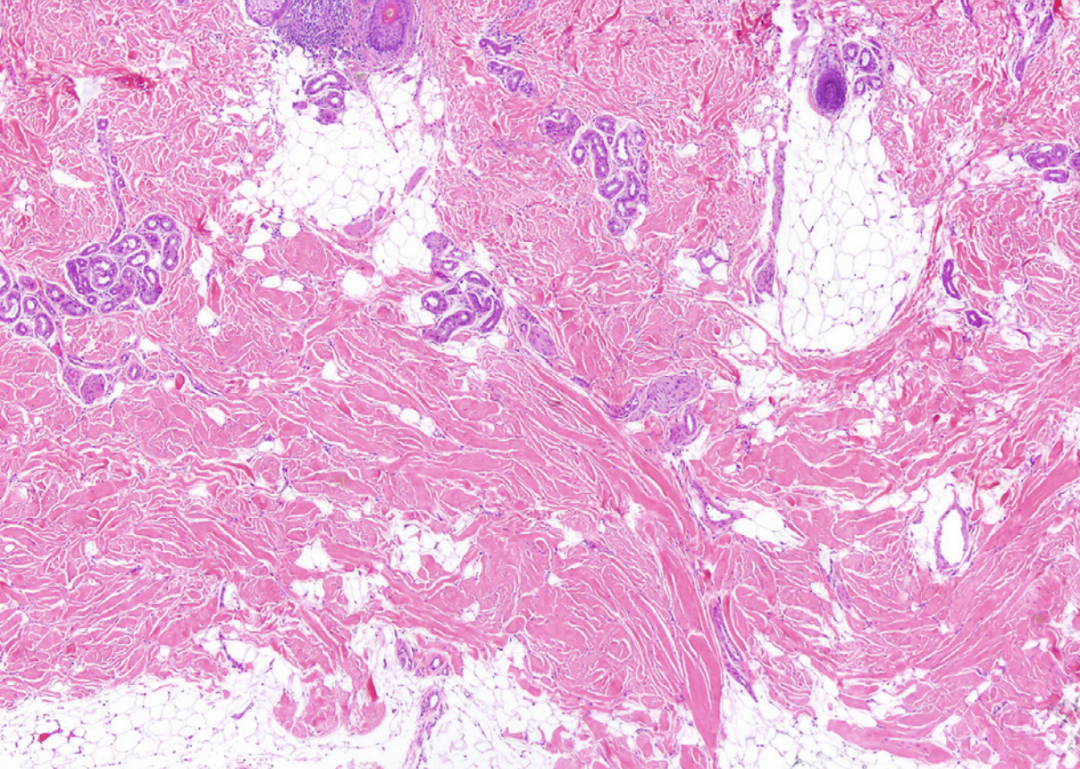

(深部硬斑:外部表現(xiàn))

最后,為了確診,必須排除自身特異性抗體的存在以及骨骼或肌肉結(jié)構(gòu)損傷等因素。診斷鑒別應主要與深部硬斑(Morphea)一起進行(深部硬斑/深部斑痕/硬皮病是一種自身免疫性疾病,通常表現(xiàn)為皮膚局限性硬化性病變)。與DFC不同,深部硬斑通常具有不對稱的分布,也很少在年輕時出現(xiàn),一般會在皮膚上會顯示可見變化。從顯微鏡觀察,膠原蛋白的排列是緊密的。此外,在早期階段常有淋巴漿細胞浸潤。在兒童全身泛硬化病變中,雖然如DFC一樣受到深度影響,但相比之下,深部硬斑的皮膚上有著非常明顯的潰瘍和色素障礙,使其易于鑒別。

(深部硬斑:真皮增厚、血管周圍淋巴細胞和漿細胞浸潤)